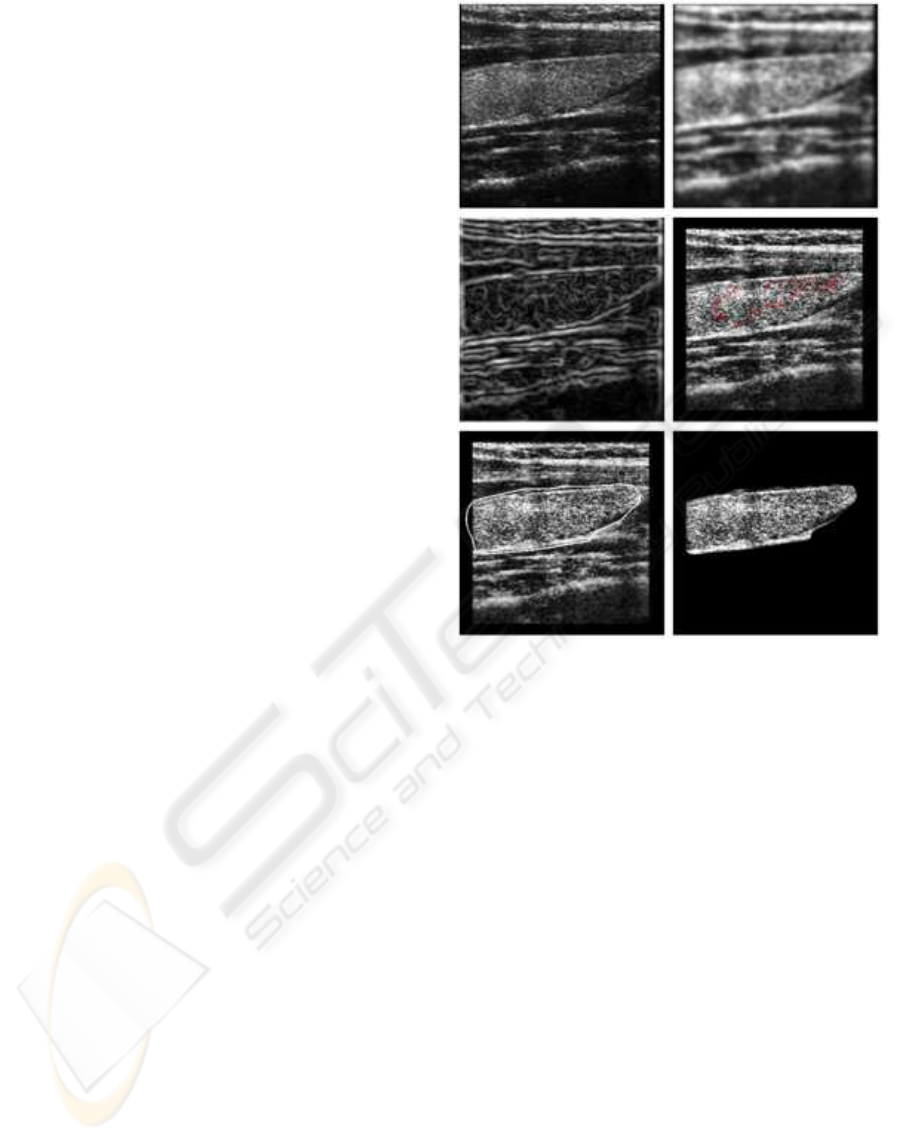

Computer derived features from 2D ultrasound im-

ages of the thyroid glands were used as part of a pro-

totype biometric system. These features are related

to the acoustic impedance, texture and morphology of

the thyroid tissue.